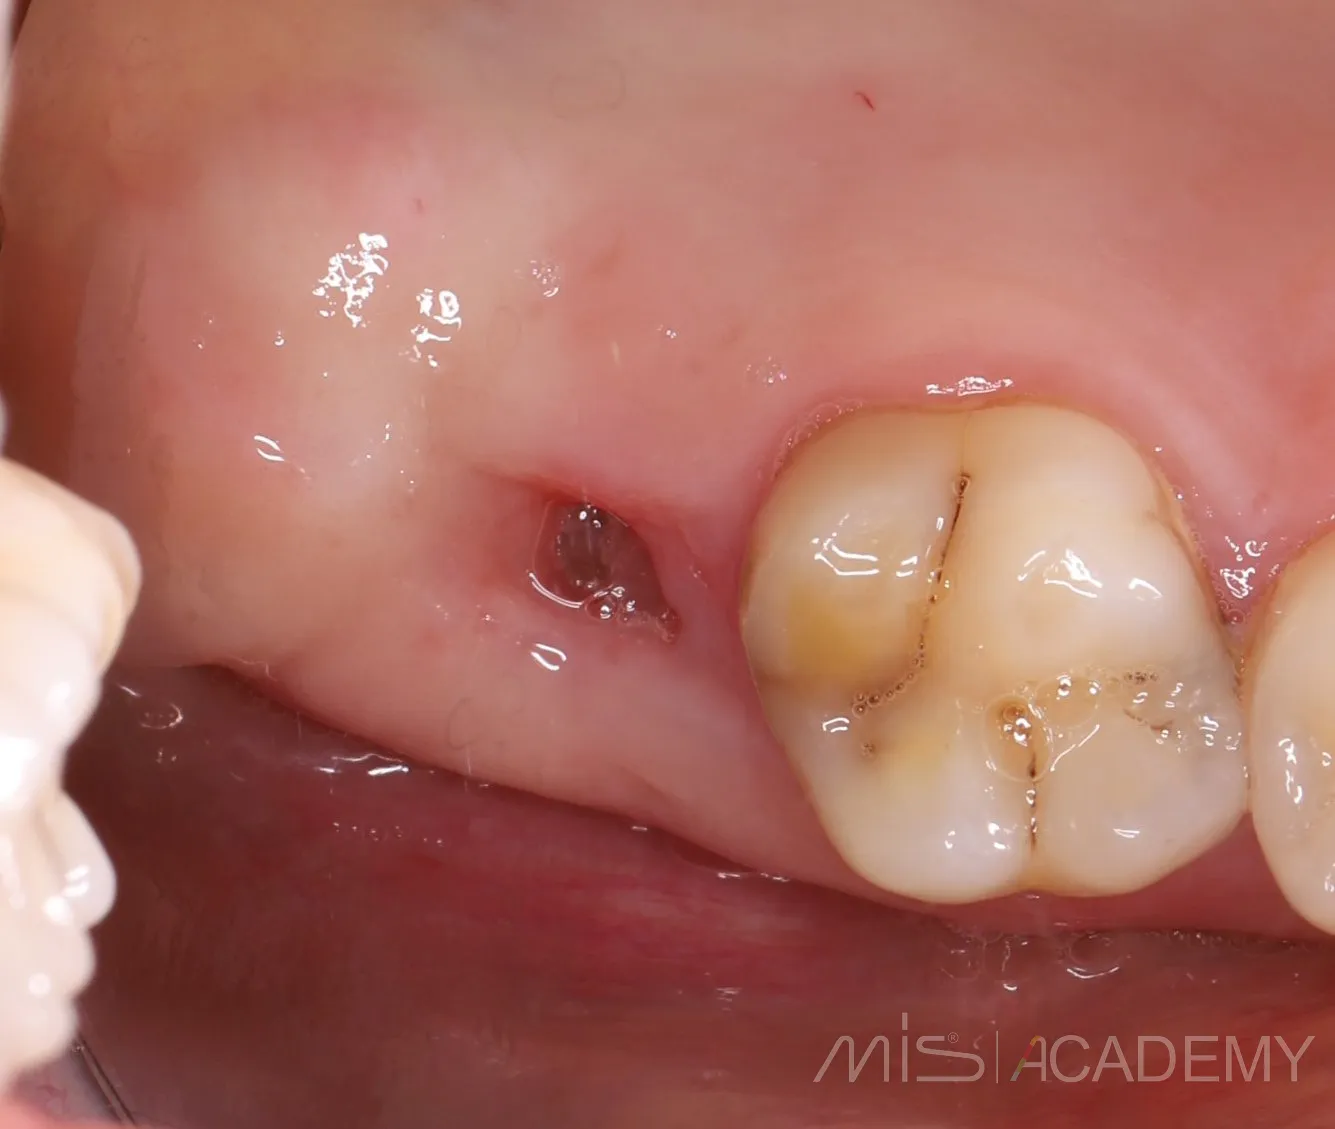

Да, я подсмотрел это способ у Артура Политова. Сейчас пациентка пришла на плановый осмотр с другой проблемой,

а зона соустья просто попала в кадр. Оказалось, что костный дефект самостоятельно закрылся и теперь там шикарные условия для ОСЛ. Ни разу не видел, чтобы соустья так закрывались. Что ж, будем теперь делать ОСЛ ..